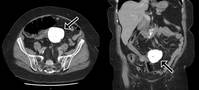

Æò¼Ò º°´Ù¸¥ Áõ»óÀÌ ¾ø´ø 70´ë ¿©¼ºÀÌ °©ÀÛ½º·¯¿î º¹ÅëÀ¸·Î ÀÀ±Þ½ÇÀ» ã¾Ò´Ù°¡ ¹è ¼Ó¿¡¼ °Å´ëÇÑ ¼®È¸ÈµÈ µ¢¾î¸®¸¦ ¹ß°ßÇÑ »ç·Ê°¡ º¸°íµÆ´Ù.È£ÁÖ ¿Ã¹ö¸® ¿öµ¿°¡ ÀÇ·á¿ø ÀÇ·áÁø¿¡ µû¸£¸é 72¼¼ ¿©¼ºÀÌ 12½Ã°£ µ¿¾È ½É..